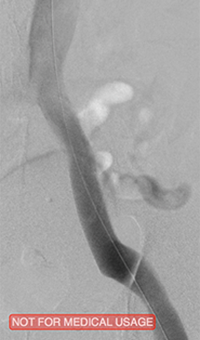

Pharmacomechanical revascularization of extensive iliofemoral thrombus

60 year old female presented with 4 weeks calf pain 1 week swelling.

Procedural steps

• Power Pulse delivery 10mg tPA

• 20 minute dwell time

• ZelanteDVT runtime 415 seconds

• Total case time 90 minutes

Xray of Iliofemoral thrombus pre-treatment and Power Pulse™ delivery

Iliofemoral thrombus pre-treatment (left) and Power Pulse delivery (right)

Xray of veins post-ZelanteDVT mechanical thrombectomy.

Post-ZelanteDVT  Mechanical Thrombectomy

Xray of veins post-ZelanteDVT runtime 415 seconds.

Post-ZelanteDVT runtime 415 seconds

Images Courtesy of Charles Wyble M.D. – Vascular Surgical Associates, Marietta, Georgia – January 5, 2016